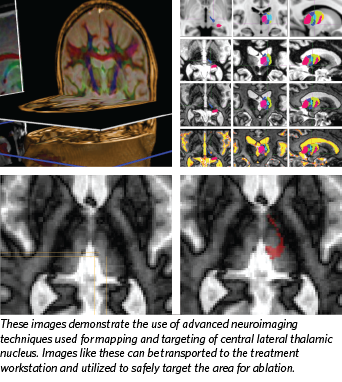

we must first understand why we are performing it. The rationale behind destroying or stimulating a neural target differs profoundly. For instance, in #trigeminal neuropathy, one should not perform a destructive RF ablation, but rather consider #neuromodulation-based 5/n